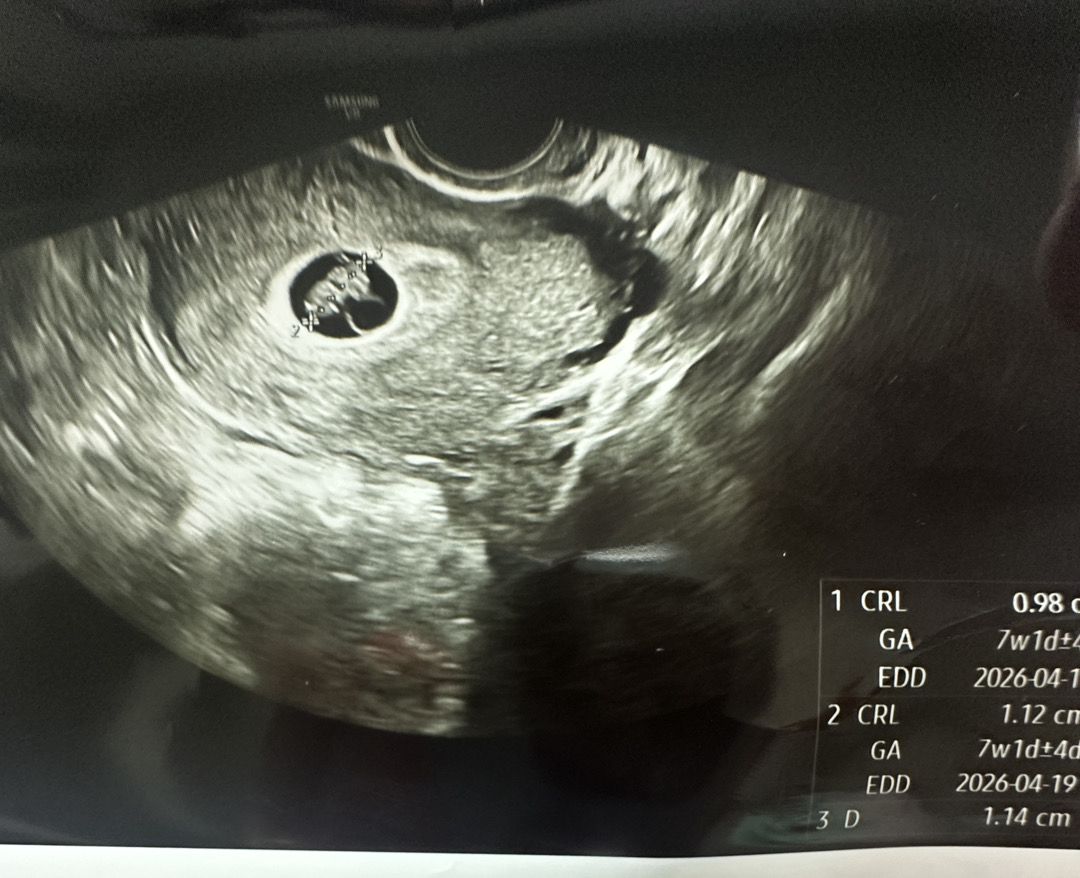

7주 들어오면서 피가 슬금 휴지에 묻어나더니 하루하루 심해지다가 이제는 패드에 한두방울씩 빨간 피가 묻기시작해요 5주도 유산 가능성있다 6주도 가능성있다 7주인 오늘도 가능성있데요 피가나는이유는 딱히 말은안하시고 6주때는 심장소리 90 오늘 은 153까지 뛰고 크기고 0.74였는데 지금은 0.98 이에요 한주한주가 스트레스고 맘을조려요 저 유산일까요?.. 아기집도 작고 난황은 너무 크다고 하고.. 다녀온뒤로 피가 좀더 난다니까 10시부터 금식후 내일 아침에 병원 오라네요..